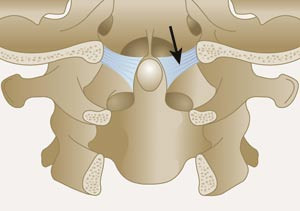

I den senere tid har mye av oppmerksomheten vært rettet mot bildediagnostisk fremstilling av strukturelle forandringer i kraniocervikalovergangen og kirurgisk behandling av antatt instabilitet i dette området. Hypotesen om en strukturell skade forårsaket av nakkeslengskade har vært gjenstand for forskning i flere år, men i en rapport fra Senter for medisinsk metodeutvikling i 2000 (3) var hovedkonklusjonen at det på det tidspunkt ikke var signifikante funn ved MR-undersøkelse av nakken ved nakkeslengskade. Etter dette tidspunkt har det imidlertid vært en betydelig utvikling innen MR-teknologi, og i nyere studier har man rettet oppmerksomheten mot støttestrukturer (leddbånd, leddkapsler og bindehinner) i overgangen mellom hodet og de to øverste nakkevirvlene. I disse arbeidene har man lagt vekt på anatomisk detaljfremstilling av ulike strukturer. De viktigste strukturene som er undersøkt med disse nye metodene er alarligamentene. Disse leddbåndene strekker seg fra toppen av C2 (dens axis) til skallebeinet. Alarligamentenes funksjon er å begrense rotasjon og sidebøyning av hodet (fig 1, 2).